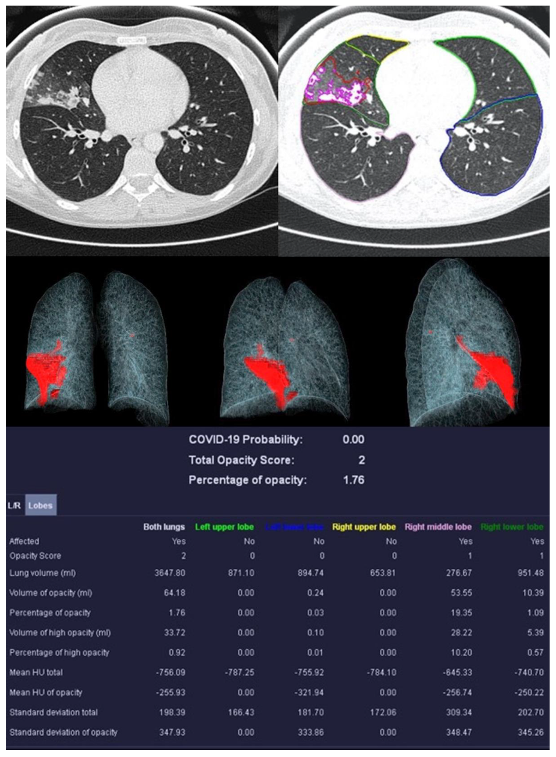

Figure 4.

Example examination of a 36-year-old patient with bacterial pneumonia caused by Heamophilus influenzae. There are flat densifications in the middle lobe corresponding to lobar pneumonia.